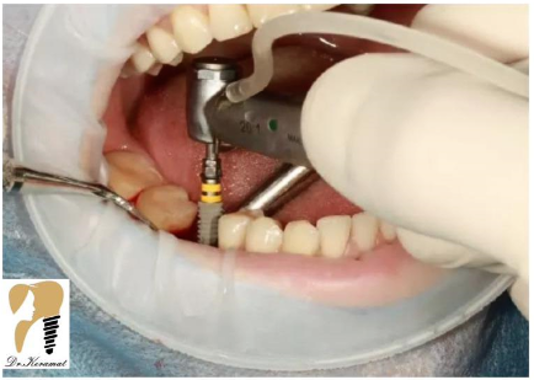

مرحله سوم: بی حسی موضعی و کشیدن ریشه دندان باقی مانده توسط دندانپزشک

مرحله چهارم: حال فک بیمار شرایط مناسبی برای کاشت ایمپلنت با استفاده از جراحی دارد و نوبت به نصب اباتمنت می رسد.